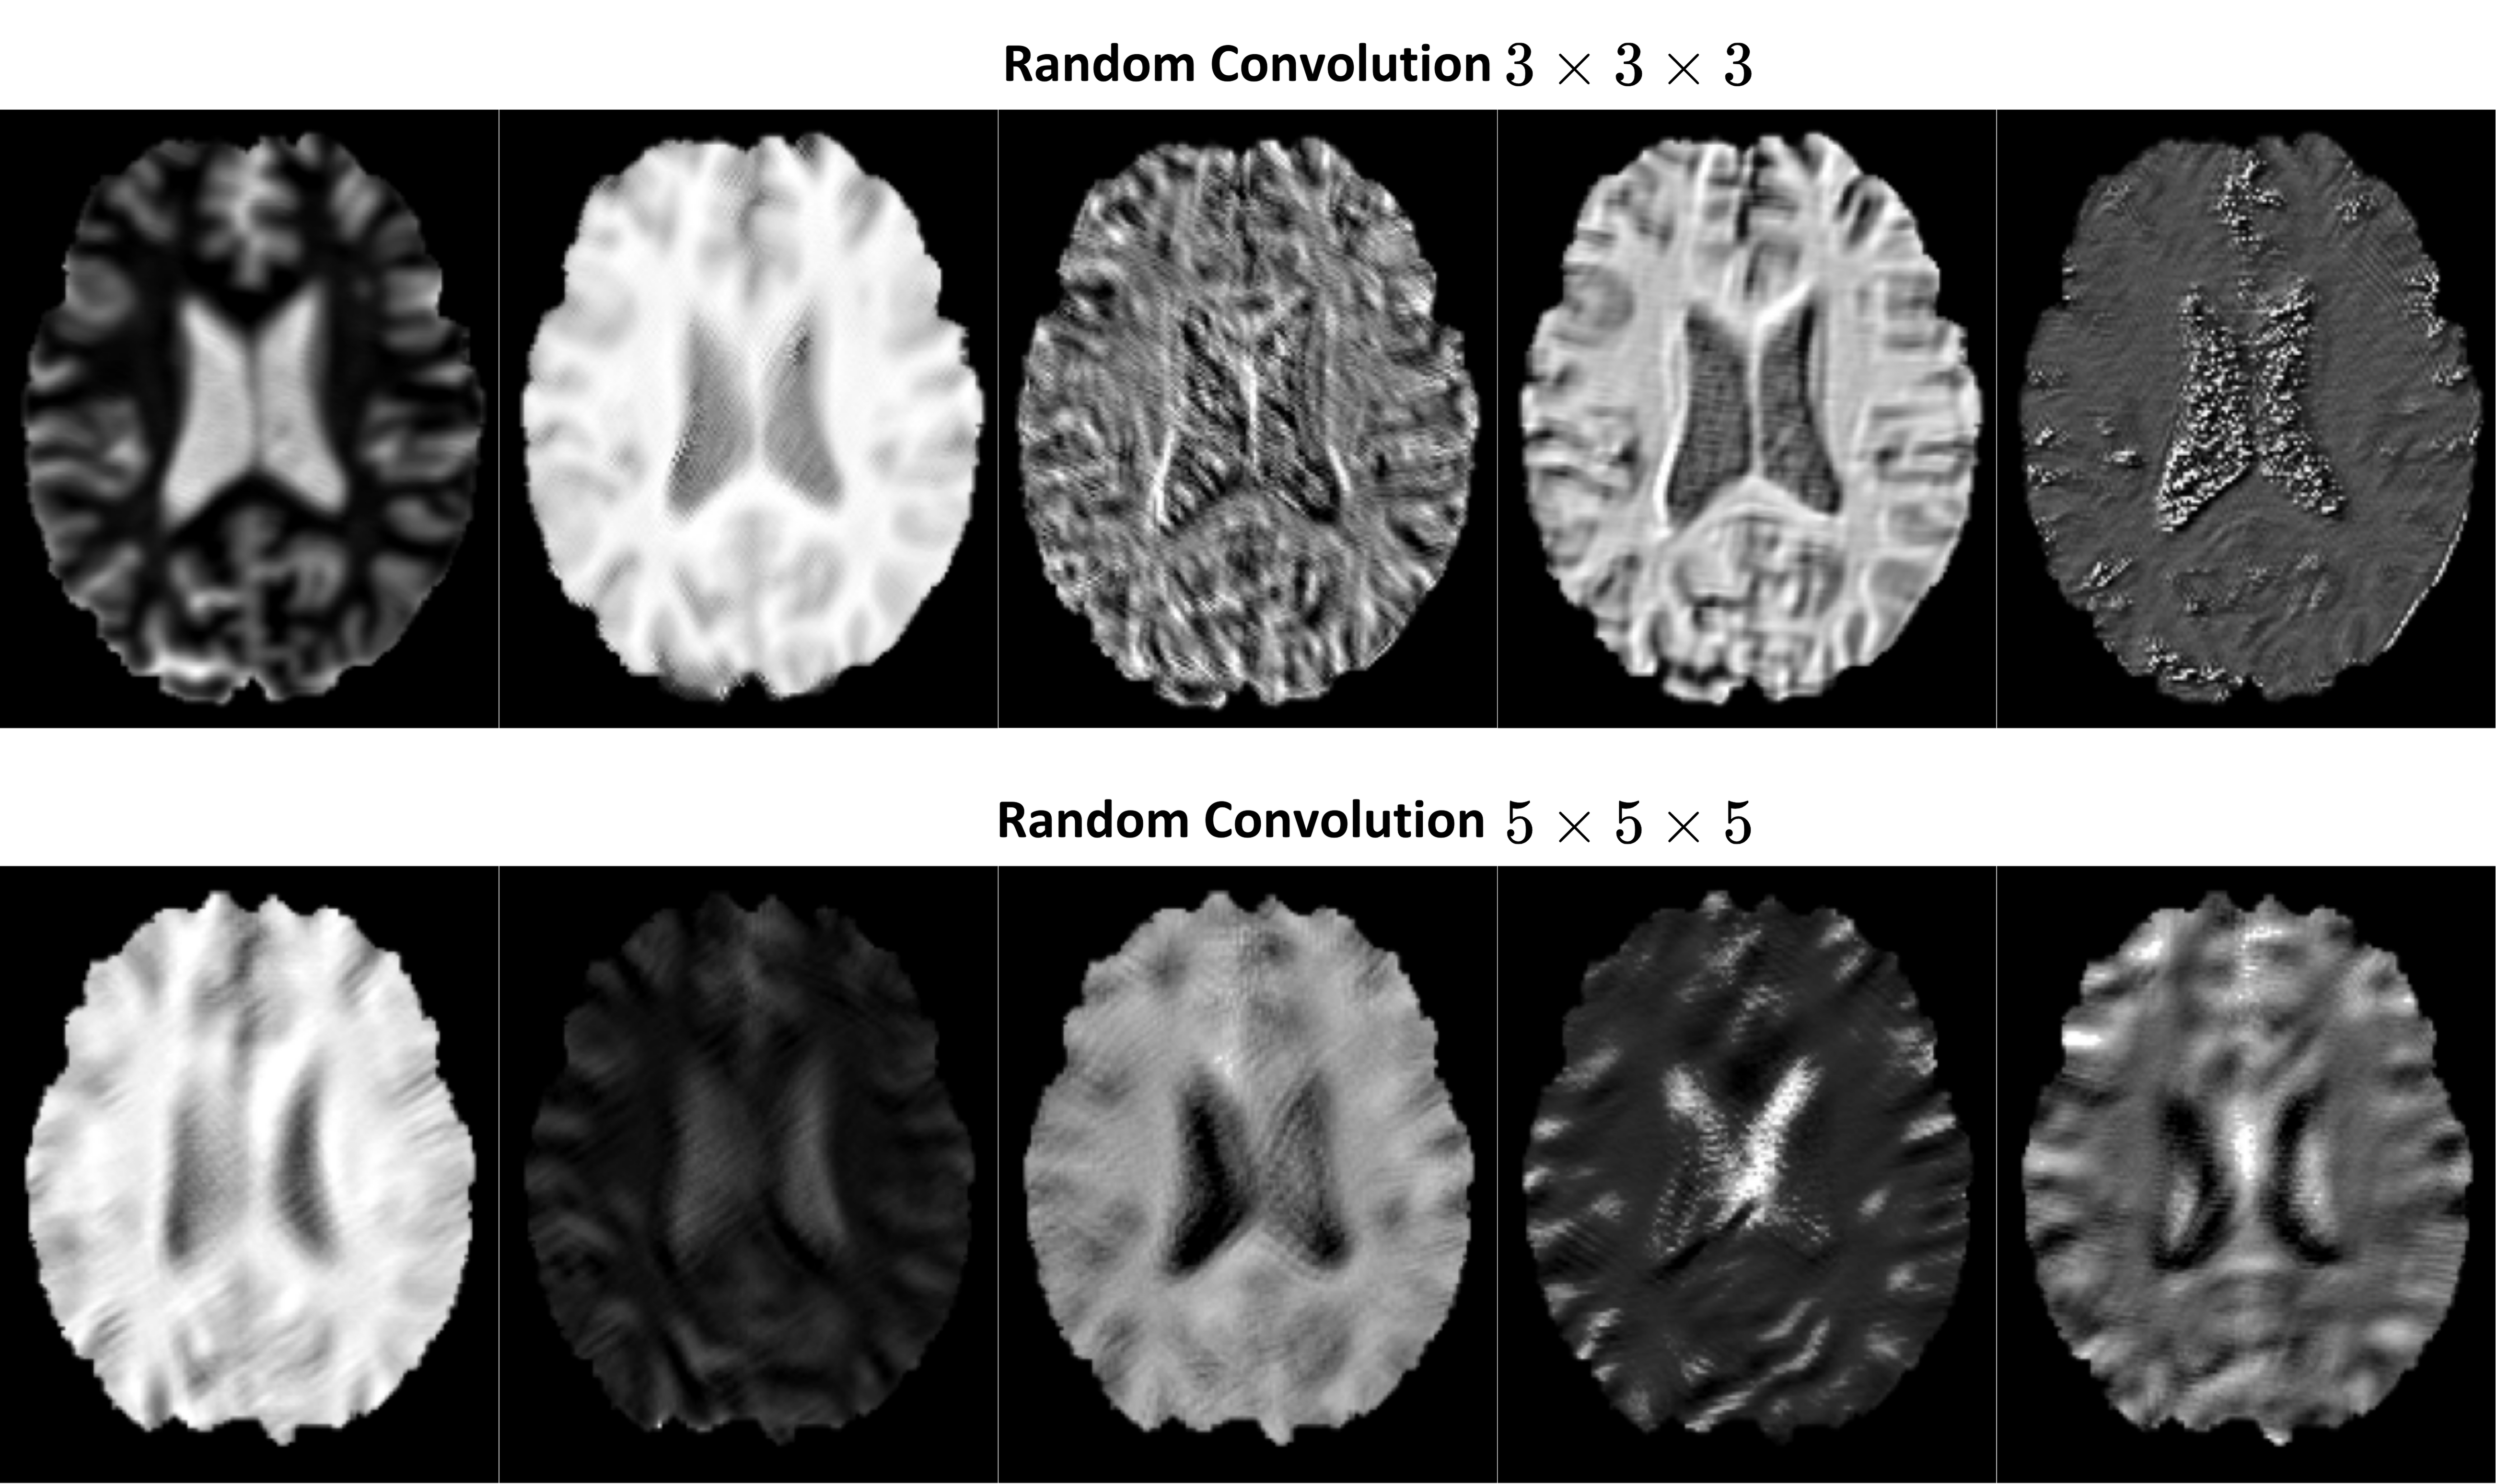

Refer to caption

Figure S3: Axial mid-slices of augmented samples generated using the RC-based contrast augmentation method with 3 ×\times 3 ×\times 3 and 5 ×\times 5 ×\times 5 convolution kernels, resulting in visible blurring effects.

To investigate the kernel size’s impact on the RC output for contrast augmentation, we have implemented the kernel size of 3×3×33333\times 3\times 3 and 5×5×55555\times 5\times 5 in all non-linear blocks of our model. Figure S3 showcases axial mid-slices of augmented samples produced using the RC-based contrast augmentation method, incorporating 3×3×33333\times 3\times 3 and 5×5×55555\times 5\times 5 convolutions. Evidently, in these samples, the augmented outputs exhibit a noticeable blurring effect, which can adversely affect the performance of the DL models. In particular, this blurring compromises precise voxel-to-voxel correspondences for our task, thereby degrading the accuracy of anatomical landmark detection outcomes.